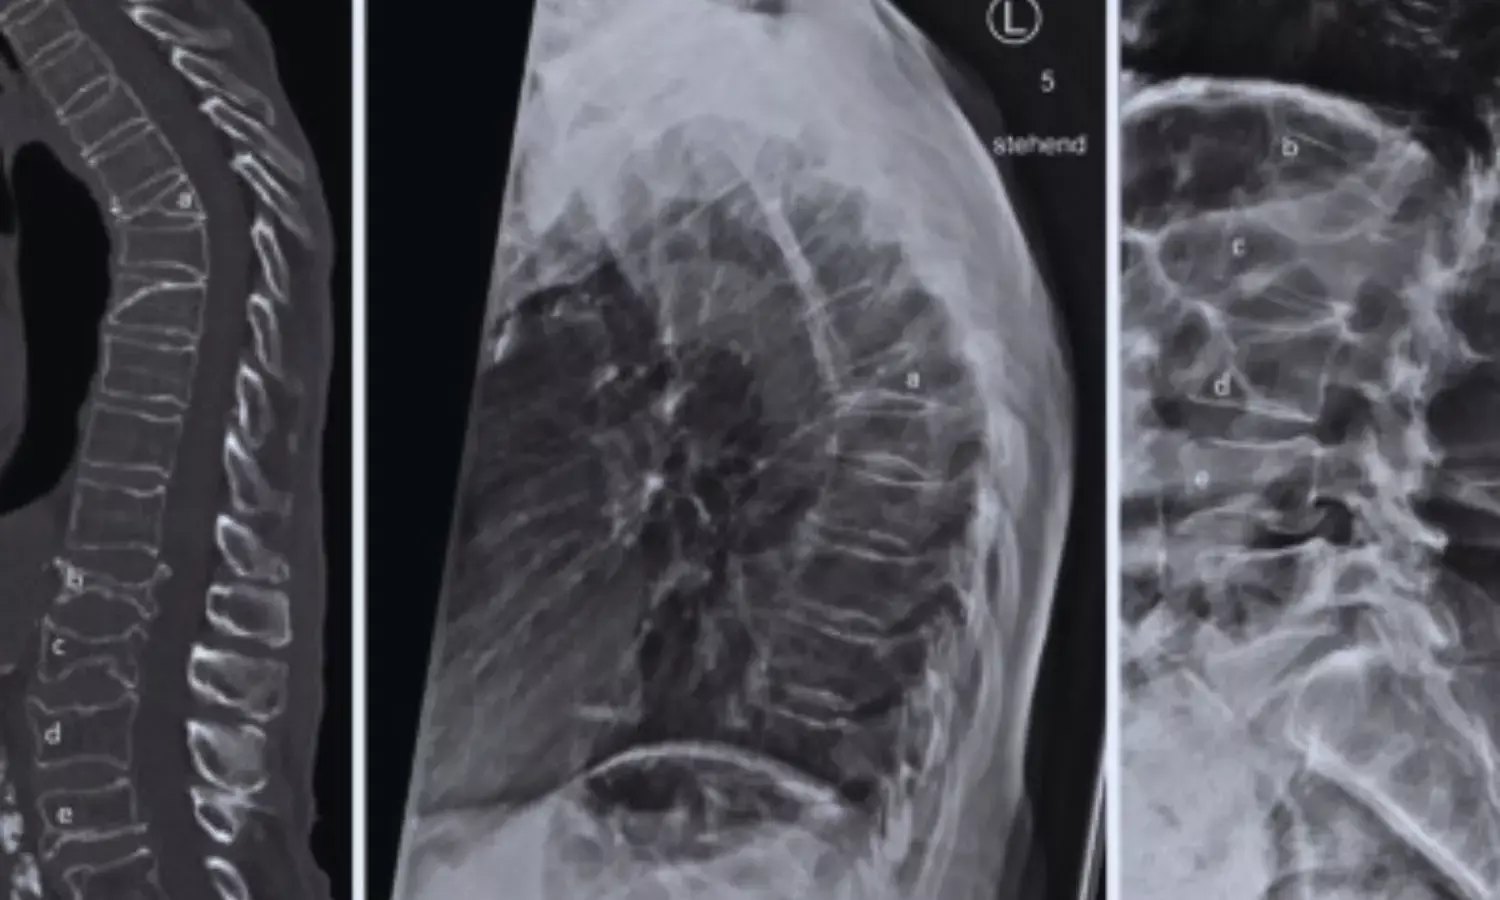

Bone loss is a well-recognized challenge of prolonged exposure to microgravity. Astronauts experience accelerated skeletal deterioration, especially in weight-bearing regions such as the spine and hip. To monitor and mitigate these effects, NASA routinely performs preflight and postflight dual-energy x-ray absorptiometry (DEXA) scans. While BMD provides information on bone quantity, TBS—derived from DEXA images—offers insight into trabecular bone microarchitecture, an important determinant of bone strength and fracture risk.

• This study represents the first use of trabecular bone score to assess spaceflight-related changes in lumbar spine trabecular integrity.